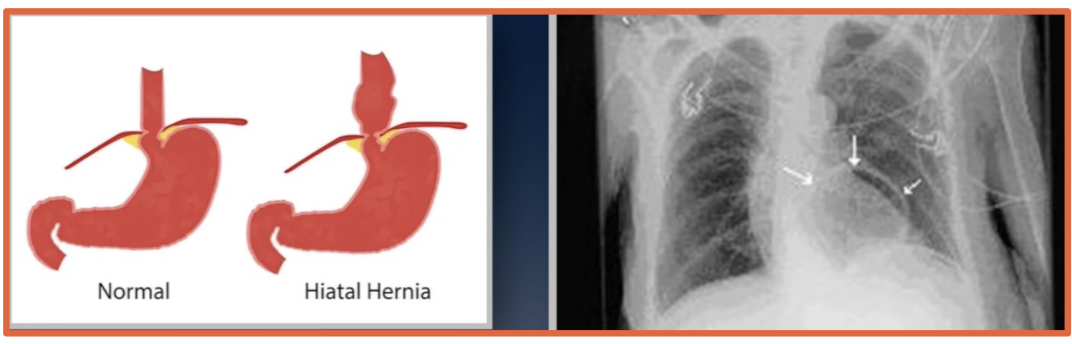

What is a hiatal hernia on chest imaging?

Part of the stomach herniates upward through the esophageal hiatus

What does free air below the hemidiaphragms on imaging mean?

Free air outside the bowel in the peritoneal cavity, usually suggesting bowel perforation